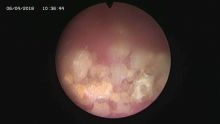

多镜联合治结石 4月6日,处于休假期间,但绥宁县人民医院泌尿外科的医护没有休息,在科主任张华生的带领下,打破常规,挑战高度,成功完成了一台复杂的结石手术。 据悉,患者姓杨,是一位60岁的男性患者,因"间断性左侧腰痛2年,再发伴尿痛2天"入院,经检查后发现患者左肾、左侧输尿管、膀胱内均有多发结石。针对这种结石,传统的手术方法至少需要开3刀,且需分期进行,使得患者痛苦大、治疗周期延长,费用也相应增高。肾结石开刀手术后劳动力会严重散失,即使采用现在流行的微创手术,常规也得分期进行,患者免不了多次手术的痛苦。为进一步减轻患者痛苦,绥宁县人民医院泌尿外科的医师们经过慎重考虑,决定打破常规,制定了多镜联合取石的手术方案。手术在4月6日顺利进行,术中联合膀胱镜、输尿管镜、经皮肾镜进行了长达70分钟的治疗,使得出血量不超过5mL且伤口仅0.5cm,一次性将患者膀胱,左侧输尿管,左肾结石全部取出。术后第五天经复查无任何结石残留,4月13日患者顺利出院。 目前,绥宁县人民医院泌尿外科在微创手术治疗各种尿路结石的技术上,己非常熟练。结石在整个邵阳地区发病率都很高,平常多喝水,每天饮水2000ml以上,调节饮食生活习惯,坚持锻炼可以有效预防结石发生,定期的健康体检也是预防结石的有效措施之一,可以早期发现结石,及时治疗。(图文 付志峰 编辑 谢雅玲) 图为:泌尿外科主任张华生、副主任付志峰进行手术时场景 图为:膀胱结石显象→手术碎石中显像→膀胱结石碎石后显像 图为:输尿管结石显像→输尿管结石碎石后显像 图为:肾结石显像→取出的肾结石标本 图为:术中建立穿刺通道 图为:术后留置的引流管 图为:术后伤口情况 |